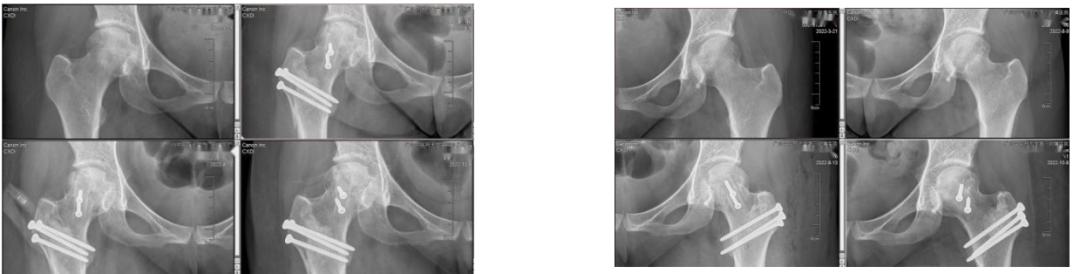

图为双侧股骨头坏死治疗前后对比图,可见双侧股骨头坏死塌陷控制、坏死修复

左侧股骨头虽然已经发生轻微塌陷,但股骨头软骨与右侧相比,无论是色泽、弹性、完整性明显好于右侧。根据我们以往的经验,疼痛时间越长、软骨损害越重,但由于左侧疼痛后进行了严格保护,虽然疼痛到接受手术的时间比右侧长,但股骨头软骨损害反而比右侧要轻,无疑是阿依按照医生的要求、下地行走时严格拄拐得到的回报。良好的软骨状态对于确保保髋疗效至关重要,从术后的复查看,阿依的已发生塌陷的双侧股骨头坏死经过保髋手术,坏死得到修复,避免了关节置换,并有望在一年内恢复正常行走。